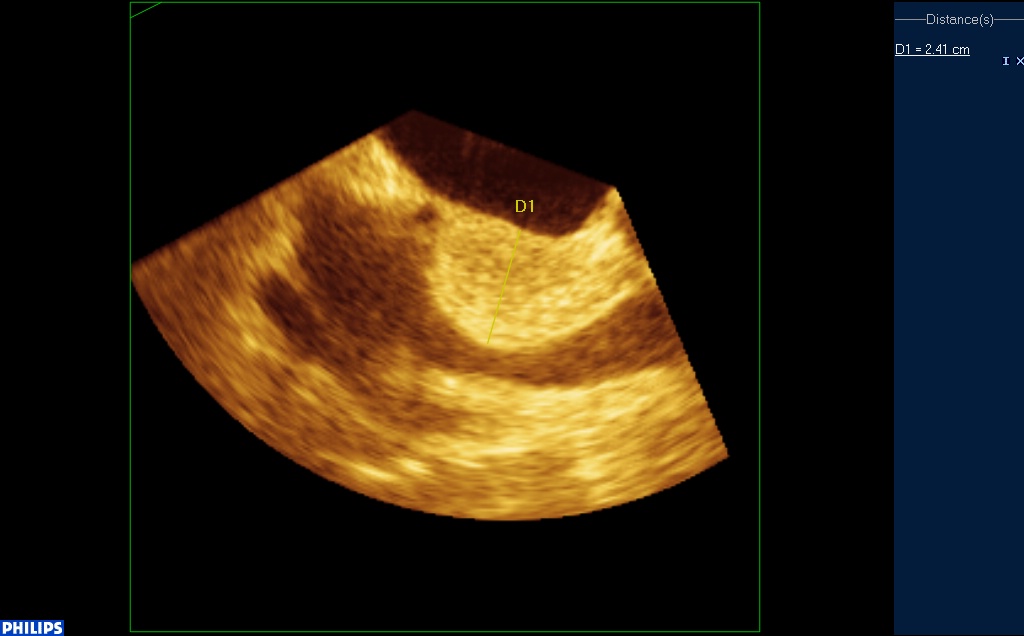

En ETO, le septum inter auriculaire est pris en masse et mesure jusqu’à 3 cm. Cette infiltration est hyperechogène, régulière, et respecte la fosse ovale.

Coupe à 120° : VCS à droite de l’écran, fosse ovale au milieu :